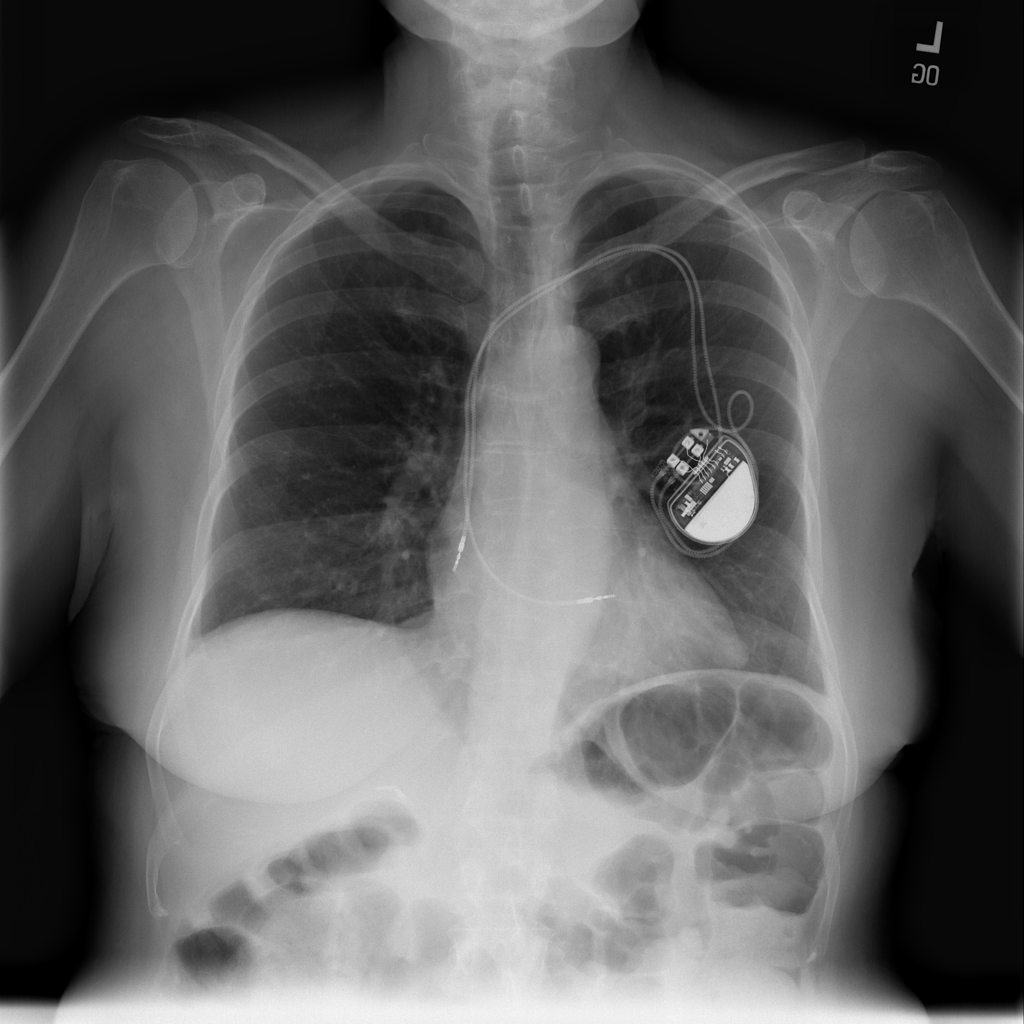

PAT-C9A4 · IMG-000Nodule

PAT-C9A4 · IMG-000

AP